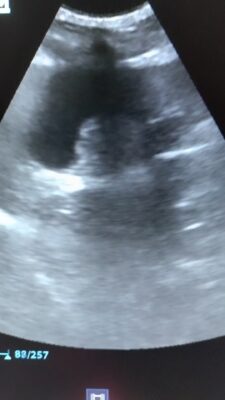

Ik heb hier een chihuahua van bijna 12 jaar, die regelmatig niet wil eten en vaak vlak na het eten onrust en pijn vertoont. Uit het bloedonderzoek komt enkel milde stijging alkalische fosfatase en een milde verhoging van de galzuren. Bij echografie zie ik in de galblaas een hyperechogene structuur die zowel bij ruglig (1e filmpje) als bij…Lees meer